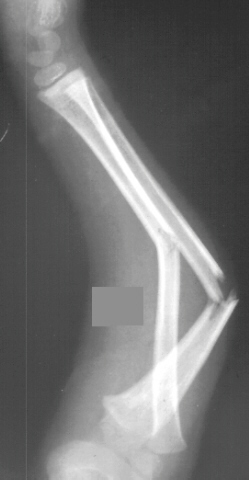

A 4 year and 6 month old male sustained a fall onto an outstretched left arm. He presented to the emergency room with forearm deformity and acute pain(image 1). It was treated with closed reduction and casting (image 2&3). The patient was brought back for another evaluation 10 months after the initial injury(image 4). An x-ray at that time was repeated. On physical examination, he has a prominence over the left radial head. There is full flexion and extension. He has full pronation but lacks 30 degrees of full supination. He is neurovascularly intact(image 5).